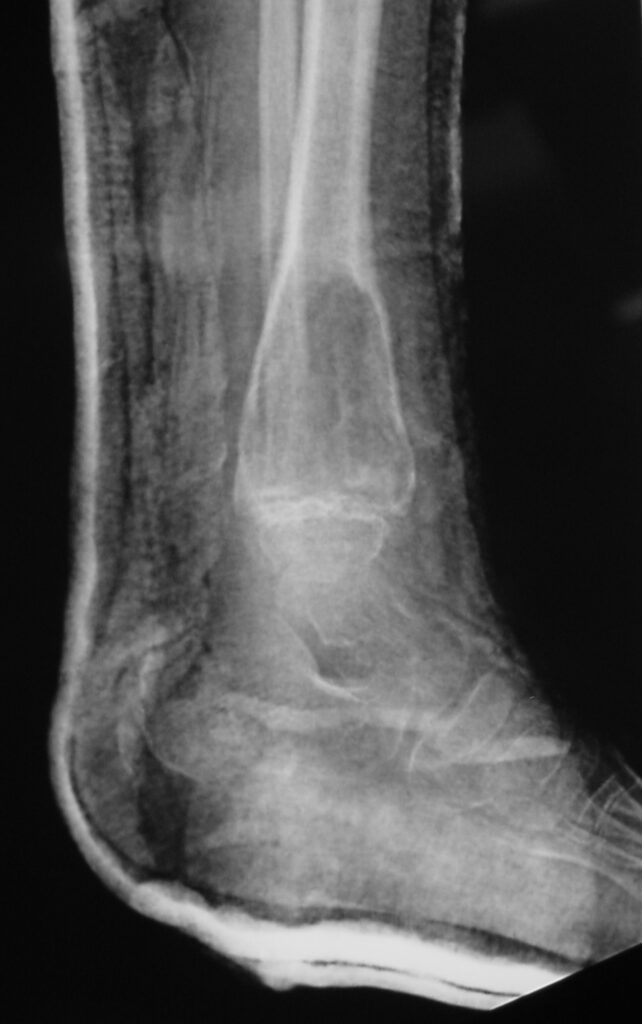

Fig 1b: Plain X-ray (Lateral View): ABC of Distal Tibia. Notice how the cortices or bony contour appears expanded. The tumor has been eroding the inner aspect of the cortex of the bone. In response the periosteum on the outside lays down new bone which gives the bone and expanded contour.